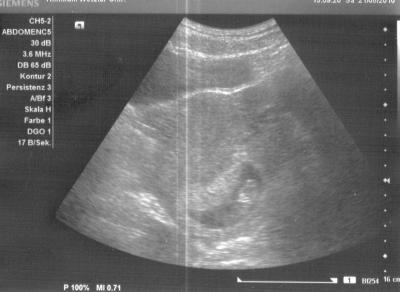

Hach war das schöööön! Endlich mal ausgiebig unser Baby bestaunt! Habens auch gleich vermessen, es misst jetzt 35 mm, also absolut zeitgerecht entwickelt *freu* Und ich hab da anscheinend nen kleinen Zappelphilipp im Bauch, es hat mit Armen und Beinen gerudert und wild gehüpft, total lustig! Leider sind die Bilder nicht ganz sooo toll, wir konnten ja nur US über die Bauchdecke machen und ich hab nen retroflektierten Uterus, der liegt also recht tief, deswegen ist der Zwergi auch so blass auf dem Bild, aber man kann ihn doch erkennen, oder? In Bewegung sieht das natürlich viiiel besser aus!

Schön, dass ihr richtig ausgiebig Baby schauen konntet... Ja, ich kann dein Baby erkennen. LG Tina